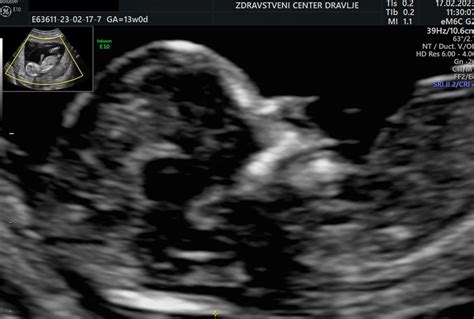

V prvem tromesečju nosečnosti, še posebej med 11. in 14. tednom, se izvaja merjenje nuhalne svetline. Ta pregled je ključen za oceno tveganja za kromosomske nepravilnosti, kot je Downov sindrom. Specialistka Ksenija Kardoš Mohorko, dr. med., spec. ginekologije in porodništva, je bila ena prvih v Sloveniji, ki je že leta 2005 pridobila mednarodno licenco za opravljanje tega specialističnega pregleda s strani Fetal Medicine Foundation. Ta pregled je še posebej pomemben pri dvojčkih.

V tem obdobju lahko z ultrazvokom že prepoznate okončine in glavico ploda ter opazujete različne vedenjske vzorce.